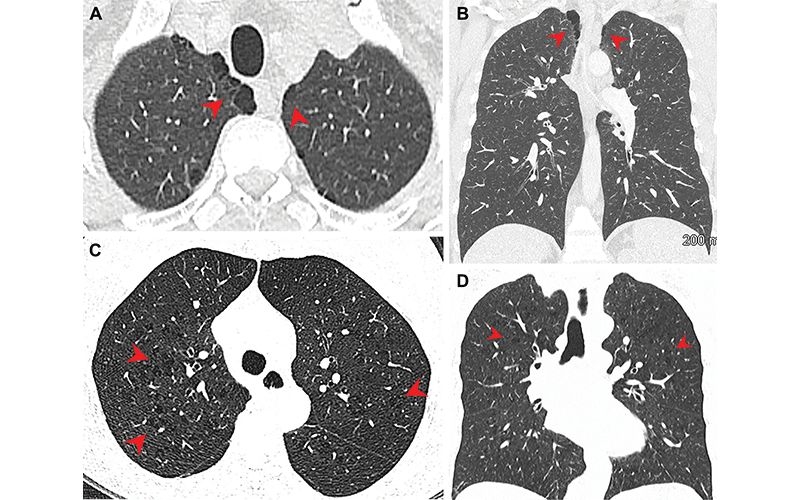

Pulmonary emphysema in (A, B) marijuana and (C, D) tobacco smokers. (A) Axial and (B) coronal CT images in a 44-year-old male marijuana smoker show paraseptal emphysema (arrowheads) in bilateral upper lobes. (C) Axial and (D) coronal CT images in a 66-year-old female tobacco smoker with centrilobular emphysema represented by areas of centrilobular lucency (arrowheads). (Murtha, et al.)

Three-quarters of the marijuana smokers had emphysema, a lung disease that causes difficulty with breathing, compared with 67% of the tobacco-only smokers. Only 5% of the non-smokers had emphysema. Paraseptal emphysema, which damages the tiny ducts that connect to the air sacs in the lungs, was the predominant emphysema subtype in marijuana smokers compared to the tobacco-only group.